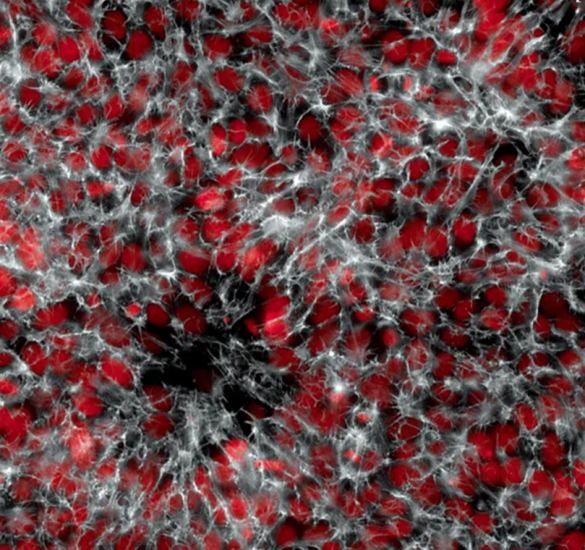

Kjo shkrepje është shumë thellë nw lëkurë. Ju po shikoni një imazh të grupimeve të melanomës metastatike.